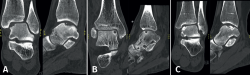

Las lesiones pueden caracterizarse por su localización, morfología y tamaño. La localización puede describirse utilizando un esquema anatómico del astrágalo de 9 cuadrículas, como el descrito por Raikin et al., que se muestra en la Figura 1(14). La morfología de una OLT puede describirse como crateriforme, quística o fragmentaria (Figura 2)(4,15,16). El tamaño de la lesión debe indicarse en el plano anteroposterior, en el plano medial-lateral y en profundidad, lo que permite calcular la superficie y el volumen de la lesión(4). Sin embargo, no hay consenso sobre la morfología de las OLT y, aunque existen sistemas de clasificación radiológica de las OLT, carecen de validación y utilizan una terminología incongruente. Además, los métodos de medición del tamaño de las lesiones varían, lo que contribuye aún más a la incongruencia en la caracterización de las lesiones en la literatura(15).

Figura 2. Tipos de morfologías de las lesiones osteocondrales del astrágalo observados en tomografía computarizada en vista coronal y sagital. A: crateriforme; B: quística; C: fragmentaria.